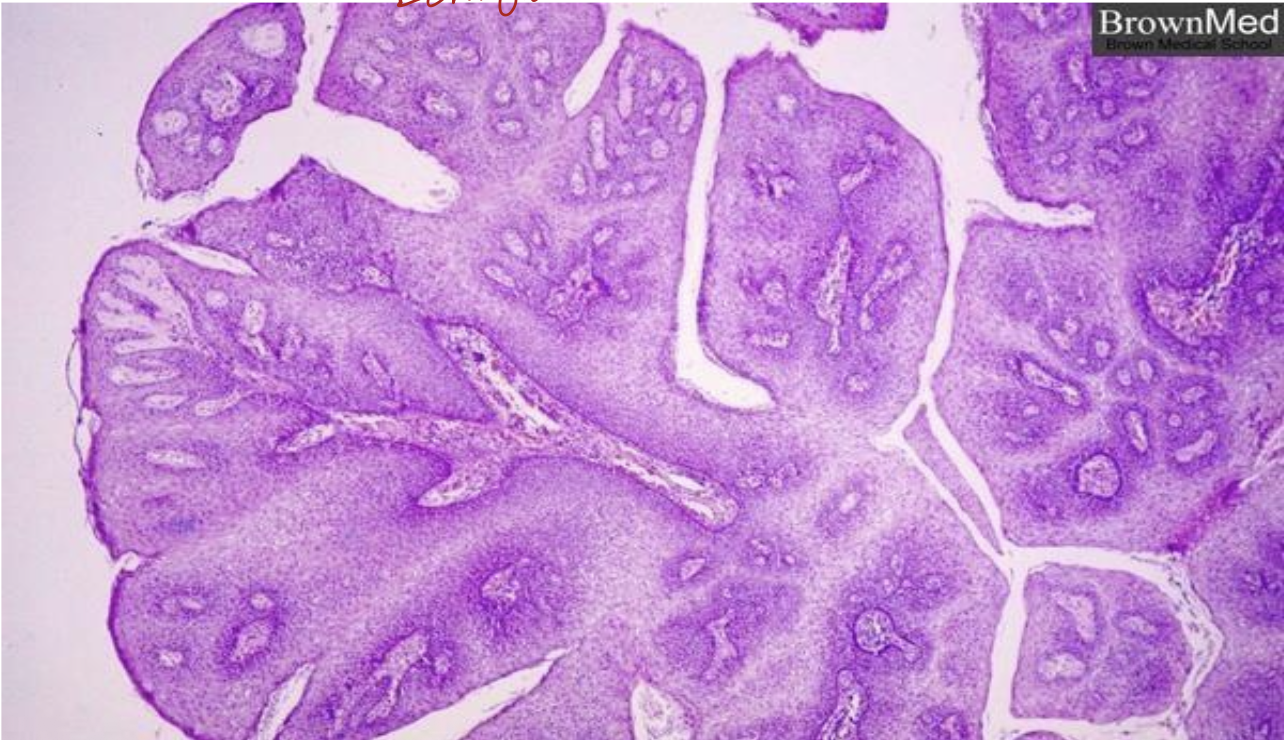

Identify the the diagnosis

squamous cell papilloma